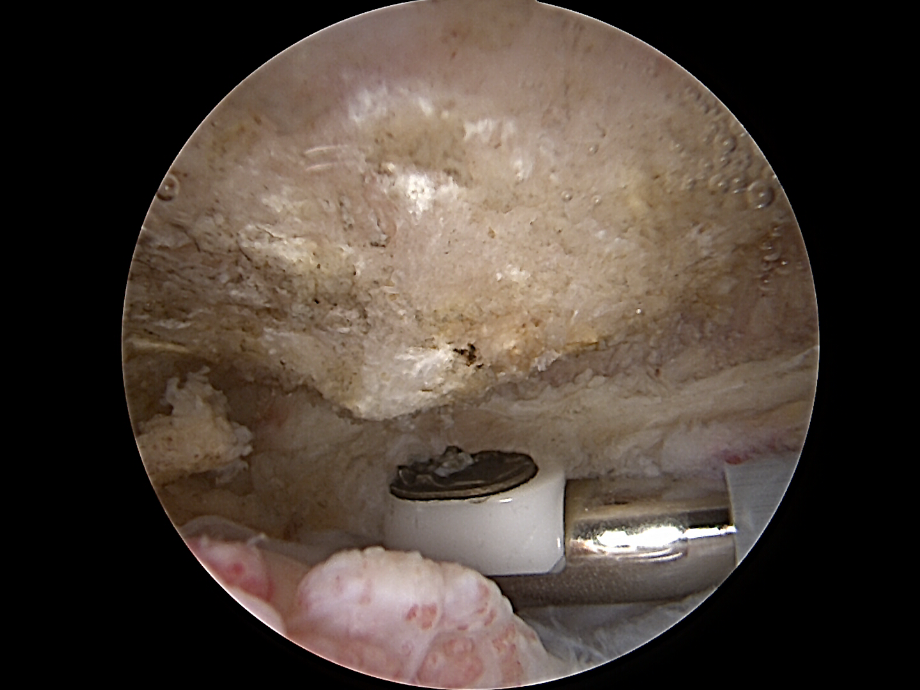

Schleimbeutel Schulter | Orthopäde 1010 | Dr. Ewald Timmel

Darstellung des Subacromialraumes

• Die Kamera wird in den subacromialen Raum vorgeschoben.

• Der oft entzündete Schleimbeutel (Bursa subacromialis) wird entfernt (Bursektomie), um Platz zu schaffen und die Sicht zu verbessern.

ac gelenkresektion von dr. timmel von ortho-timmel.at